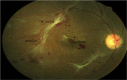

Figure 3

Proliferative diabetic retinopathy. Colour fundus photograph showing (A) new vessels, (B) fibrovascular tissue and (C) a central retinal hole secondary to traction from fibrovascular tissue.